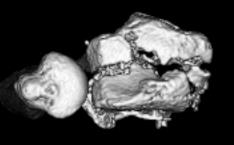

レントゲン検査やCT検査で行い、骨折型やずれの大きさを評価します。治療方法を骨折型やずれの大きさによってお勧めします。

- ▼手関節CT 末梢側から

- ▼手関節CT 掌側から

※関節内にも骨折線を認めています。